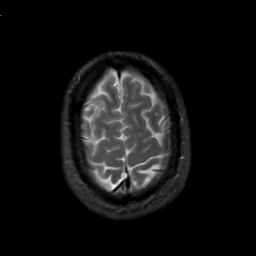

MR Study #2, February 17, 1991 -- Slice #43

[Home][Help][Clinical][Tour 1][Tour 2] Slice 43